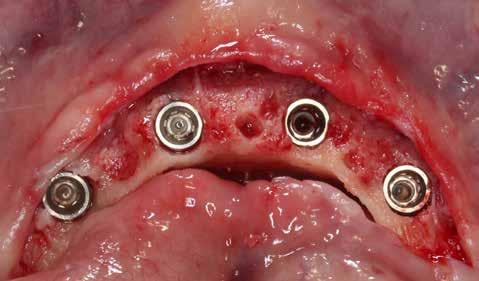

1. ábra: Műtét előtti fogászati panorámafelvétel, amelyen a hiányzó felső állcsont jobb első premolárisát és a szabad véggel rendelkező hidat láthatjuk. — 2. ábra: Az implantátum méreteinek megtervezése CBCT-vel. 3. ábra: Bukkális lágyrészdefektus. — 4. ábra: A biológiai szélesség értékelése a vertikális lágyszövetvastagság alapján. 5. ábra: Palatinális „tekercslebeny” – Palatal roll flap. — 6. ábra: Bredent medical copaSKY 4x10 implantátumbeültetés. 7. ábra: Szubkresztális implantátumbeültetés a várható biológiai szélességnek megfelelően.

8. ábra: Egyéni ínyformázó titánbázison, tulipán alakú emergenciaprofillal. — 9. a. ábra: A sebzárás okkluzális nézete.

bukkális nézete.

9. b. ábra: Feszülésmentes zárás

8 9a 9b 10 12a 13 11 12b 14